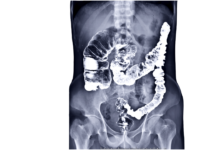

Constipation is a common digestive issue characterized by infrequent, difficult, or painful bowel movements. It occurs when the stool becomes hard and dry, making it harder to pass. Typically, a person is considered constipated if they have fewer than three bowel movements per week. Other symptoms may include a bloated feeling, abdominal discomfort, and straining during bowel movements.